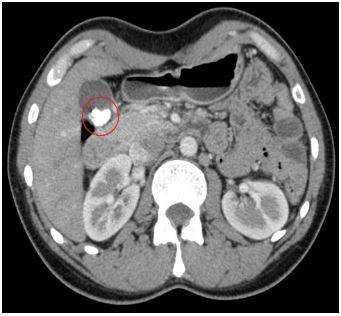

![Конкременты в желчном пузыре при КТ]()

Конкременты в желчном пузыре при КТ

КТ обнаруживает примерно 75% камней в желчном пузыре и протоках. Чувствительность способа зависит от состава конкрементов.

Результаты компьютерного сканирования не позволяют увидеть мягкие камни, но плотные конкременты визуализируются на томограммах хорошо.